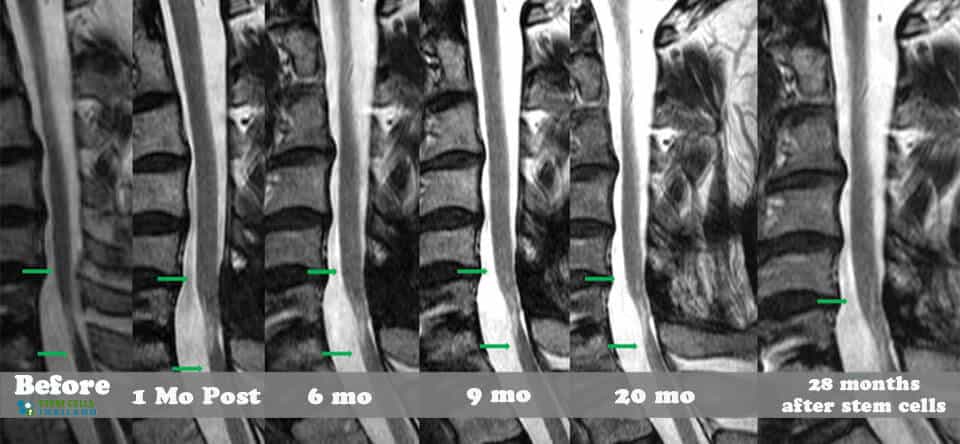

治療目標(biāo)和預(yù)期結(jié)果

組織、軟骨或韌帶的新?lián)p傷對(duì)干細(xì)胞治療的反應(yīng)要好得多。治療后的康復(fù)需要大量的奉獻(xiàn)和康復(fù)訓(xùn)練。初次治療后約2-3個(gè)月,身體改善明顯,且效果是永久性的。[2]